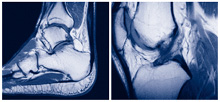

Kernspintomographie

Die Kernspintomographie eignet sich hervorragend zur differenzierten Diagnostik u. a. von Gelenkerkrankungen. Mit Hilfe von Magnetfeldern und Radiowellen werden ohne Strahlenbelastung detailreiche hochauflösende Schnittbilder Ihrer zu untersuchenden Körperregion erzeugt.

Die Kernspintomographie eignet sich hervorragend zur differenzierten Diagnostik u. a. von Gelenkerkrankungen. Mit Hilfe von Magnetfeldern und Radiowellen werden ohne Strahlenbelastung detailreiche hochauflösende Schnittbilder Ihrer zu untersuchenden Körperregion erzeugt.